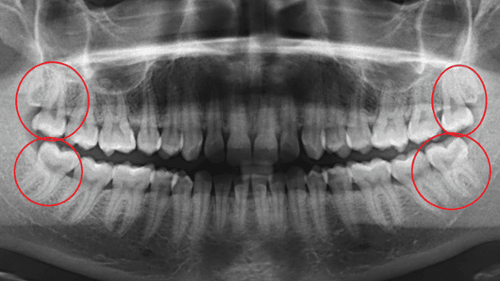

About 75% of Australians today don't have enough space in their mouths for these last four teeth to come in properly. When they get stuck, they are said to be "impacted," and this can hurt, swell, or infect the healthy teeth around them. It's kind of like a puzzle where the pieces don't fit together anymore.

Often it makes sense to get rid of wisdom teeth before they become a problem. When impacted teeth push against your second molars, they can break down or get cavities that are very hard to fix, and sometimes result in losing the second molars too. In addition, these teeth are very hard to clean because they are so far back.

When you ask, "Should I get my wisdom teeth taken out?" the answer should be based on a combination of professional opinion, radiographic (X-Ray) imaging, and how comfortable you feel with the idea. There are different kinds of faces.